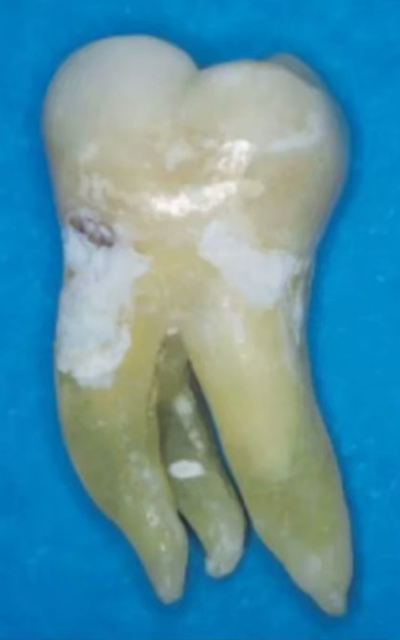

異于雙根的下頜第一磨牙的解剖形態(tài)變異主要為存在一個(gè)額外的位于遠(yuǎn)舌側(cè)【radix entomolaris(RE)】或近頰側(cè)【radix paramolaris(RP)】的牙根(圖 13)。在白種人和非洲人中發(fā)生這種牙根異常形態(tài)的概率不超過 5%,然而在黃種人中(比如中國(guó)人、因紐特人、印第安人)遠(yuǎn)舌根發(fā)生率在 5%至超過 30%之間。位于頰側(cè)的近頰根罕見,發(fā)生率低于 0.5%(。遠(yuǎn)舌根的外形大小可從小圓錐形變化至正常長(zhǎng)度和根管的“成熟的”牙根。

一般來說,遠(yuǎn)舌根比遠(yuǎn)頰根和近中根小,可能獨(dú)立于或部分融合于其他牙根。臨床治療過程中,當(dāng)懷疑存在額外的牙根時(shí),需要根據(jù)準(zhǔn)確的放射學(xué)診斷、臨床檢查、開髓洞型預(yù)備進(jìn)行判斷。在術(shù)前的放射片中,若遠(yuǎn)中根輪廓或根管的視野或外形不清楚,可能表明存在“隱藏的”牙根。在近中或遠(yuǎn)中成 30 度角的方向上拍攝第二張放射片,通??梢燥@示遠(yuǎn)舌根的輪廓。

使用牙周探針對(duì)牙冠或牙頸部形態(tài)進(jìn)行臨床檢查有助于發(fā)現(xiàn)額外的牙根。一個(gè)額外的牙尖(副磨牙結(jié)節(jié),tuberculum paramolare)或明顯突出的遠(yuǎn)頰或遠(yuǎn)舌小葉,伴有頸部的突出,可能表明存在額外的牙根。遠(yuǎn)舌根的根管口位于主要的遠(yuǎn)中根管的近舌側(cè),因此開髓洞型需要預(yù)備成矩形或梯形。使用牙髓探針仔細(xì)檢查髓室底的暗色的發(fā)育溝,可以精確的定位遠(yuǎn)舌根根管口。